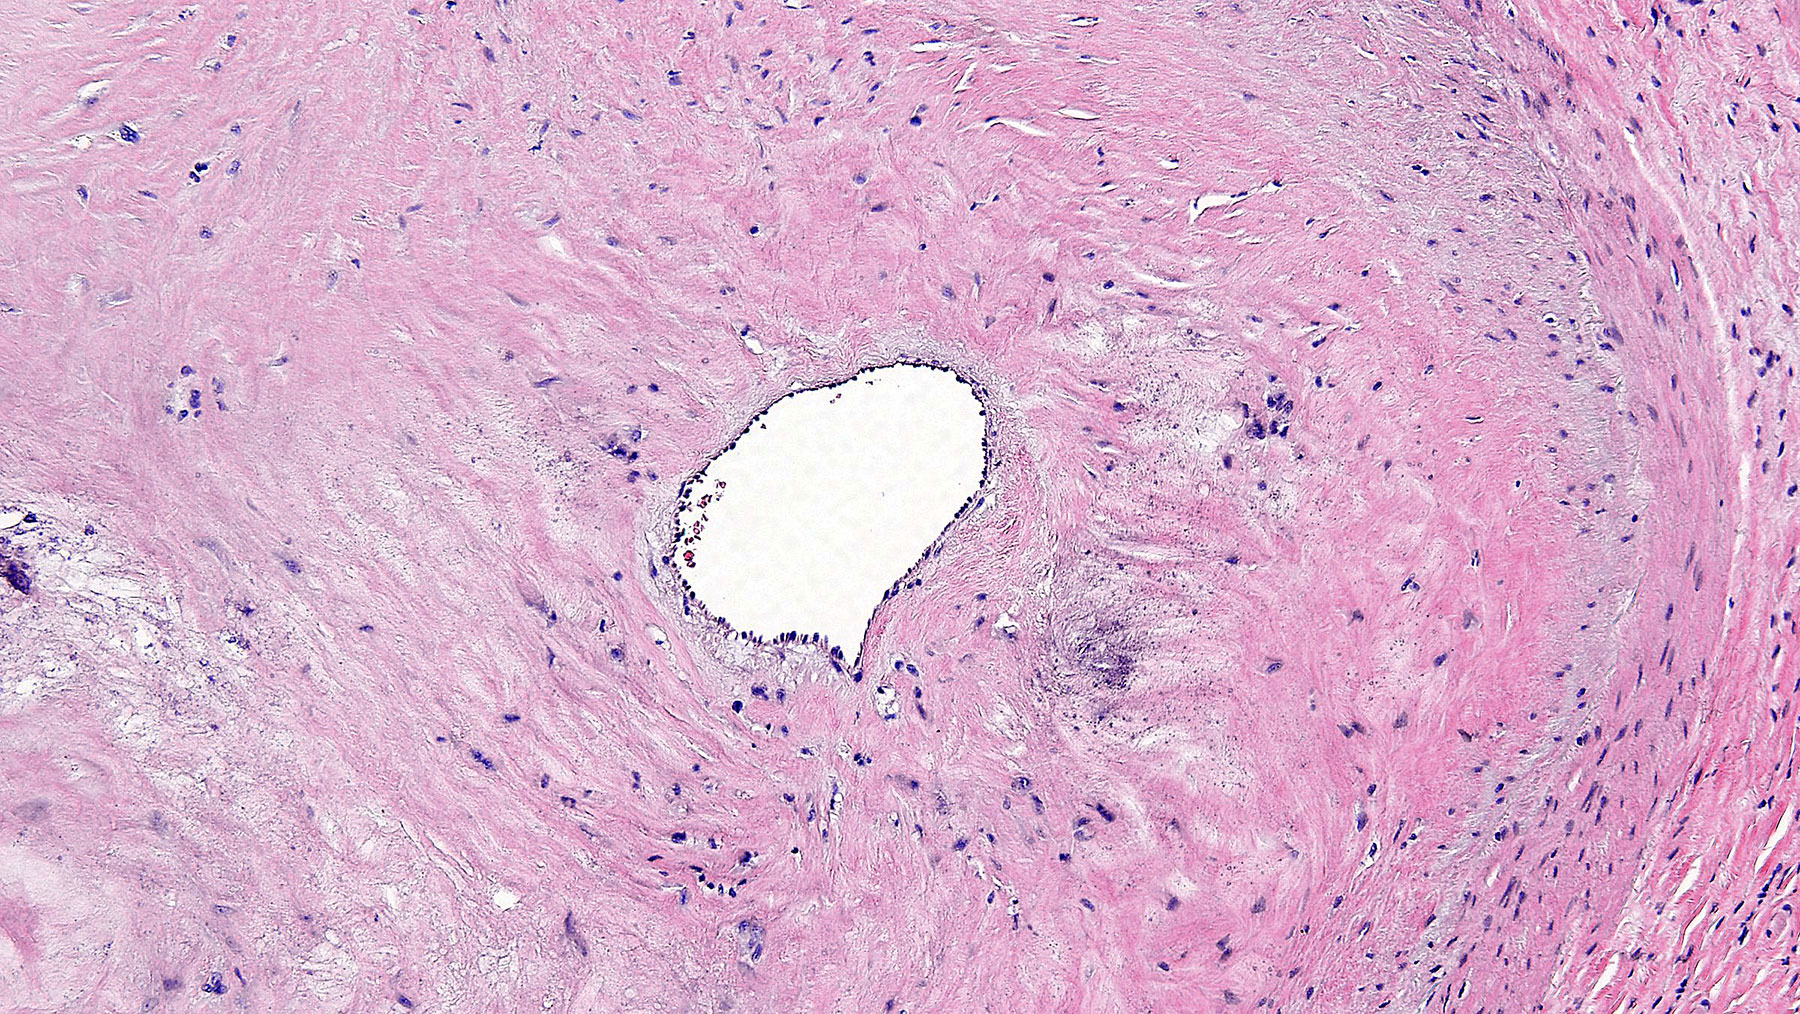

Figure C. H&E x10

Histology: Figure A shows coronary artery atherosclerosis with dystrophic calcifications on upper left hand side of the figure A (Calcifications appear bluish on H&S staining). There is >90% occlusion of the lumen (lumen shown by the arrow). Figure C shows the endothelial lining of the lumen. The fibrosis is confirmed by trichrome staining in Figures B and D.  All these finding are consistent with severe coronaryartery disease